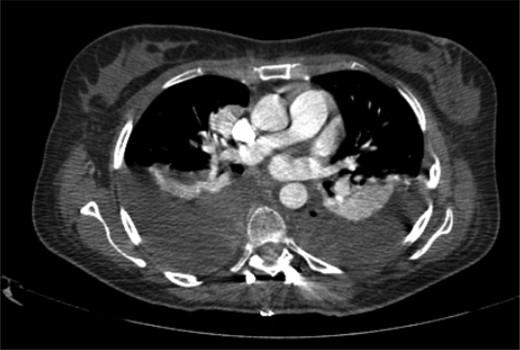

The patient started the pulmonary rehabilitation protocol by the second postoperative day, showing encouraging progression. However, by the third day, she initiated complaints of progressive dyspnea with associated impaired gas exchange. A CT scan confirmed bilateral hemothorax requiring bilateral thoracentesis (Fig. 4), after which she immediately recovered from the previous symptoms.

It was only by the 19th postoperative day, which the patient showed worsening of her general status with fever, dyspnea, decreased gas exchange and an increase in inflammatory markers. A new CT scan was performed, revealing a moderate fluid collection in both lungs, compatible with empyema (Fig. 5). The patient evolved to a septic state, which required her to be transferred to the intensive care unit.